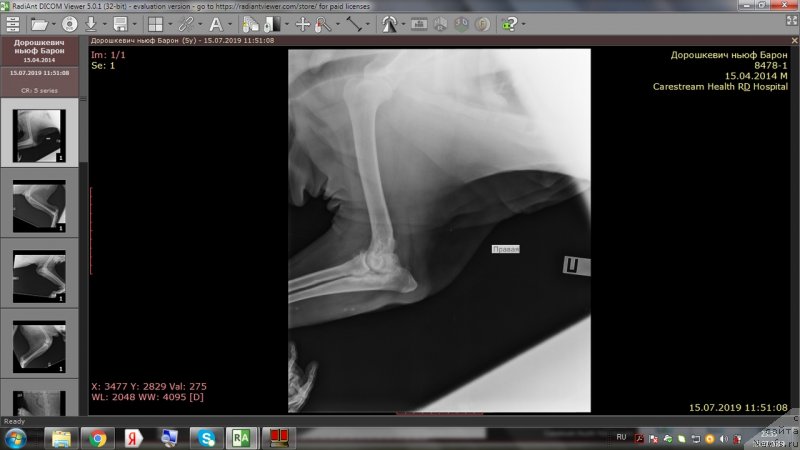

На приёме у врача.

Сейчас у доктора

Бароша врачам всем нравится))))

Доброе утро,уважаемые форумчане!Вот и проползли черепашкой эти томительные 2 недели до повторного приема врача.И,вновь,к нашей радости,не подтвердились самые худшие опасения😊.Барошенька похудел на 3 кг.На снимках,как видно,в более-менее живом состоянии только правое колено.Локти не сгибаются из-за махровых наростов,с левым коленом ситуация хуже остальных лап,на прогулке,после лежания,первые несколько метров в колене слышно перестукивание суставов,но потом все проходит.Лечение идёт на пользу,колени стали лучше сгибаться,огромный отёк с левого колена спал,и писает теперь не приседая полностью до земли и не плюхаясь пузом от усталости в свою лужу.На прошлой неделе созванивались с доктором и немного подредактировали терапию-отменили тобрекс,т.к.не было результата и заменили на офтагель,флоксал,в связи с тем ,что у Бароши синдром сухого глаза и заворот века(рекомендовано в будущем провести операцию).Сегодня обновлю запасы этих лекарств.Антибиотик доксифин продлили до 8 недель,но купила пока на 2 недели,т.к.финансов не хватит на такой курс.Полное,качественное восстановление займет месяца 2.Сейчас то тут,то там выскочит экзема,соскоб с экзем показал наличие грибов-коки,эзофилы.Тут и стресс перенесенный и смена климата и т.д.